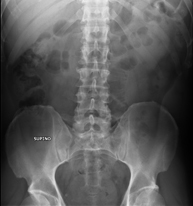

- Abdomen X-ray

This technique uses X-ray rendered imaging for examining the abdomen (stomach, small intestine, large intestine, liver, kidneys, bladder, bony pelvis, etc.).

- Pelvis X-ray

This procedure uses X-ray imaging to examine the pelvis, especially the pelvic bones.

An abdominal X-ray uses a small dose of radiation to obtain a two-dimensional image of the abdomen with its anatomical structures (stomach, small intestine, large intestine, liver, pancreas, kidneys, bladder, bony pelvis, etc.).